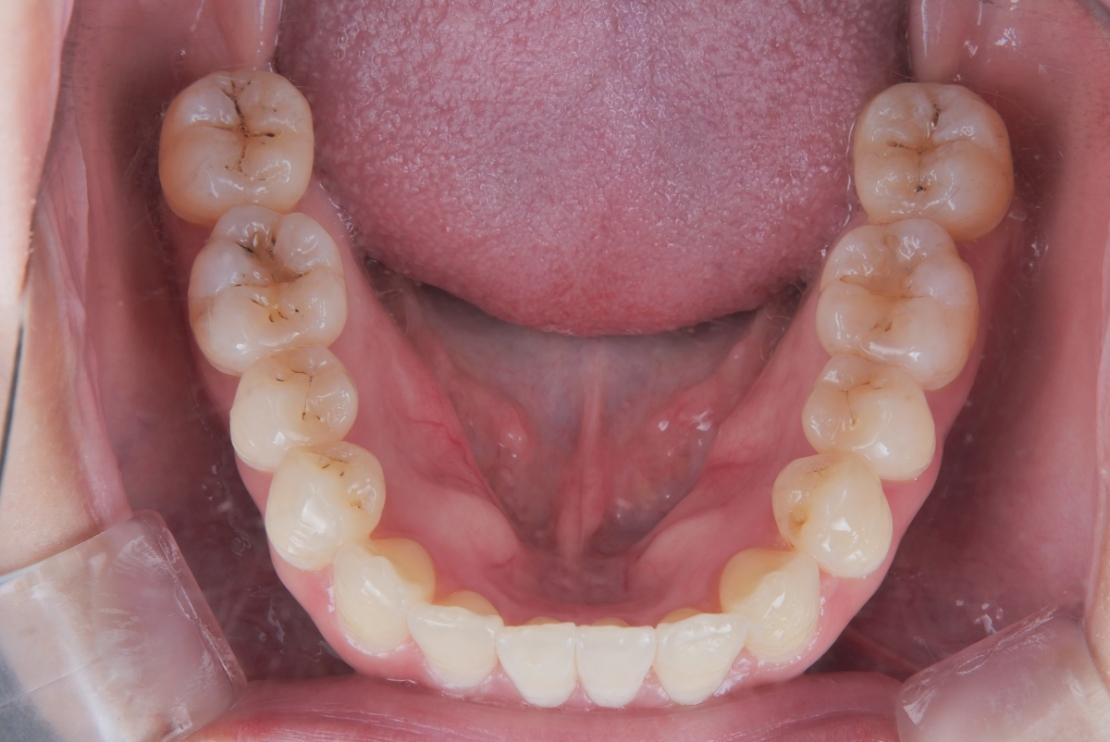

BEFORE

AFTER